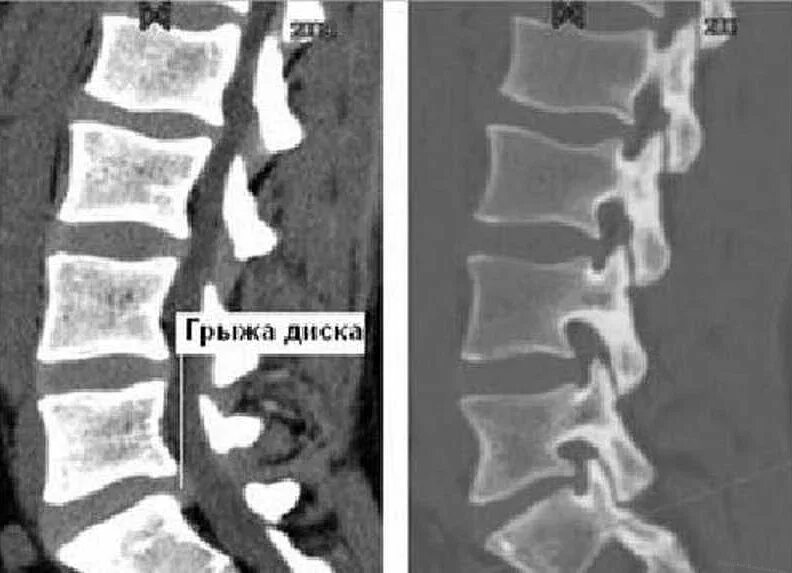

Мрт или кт позвоночника при болях